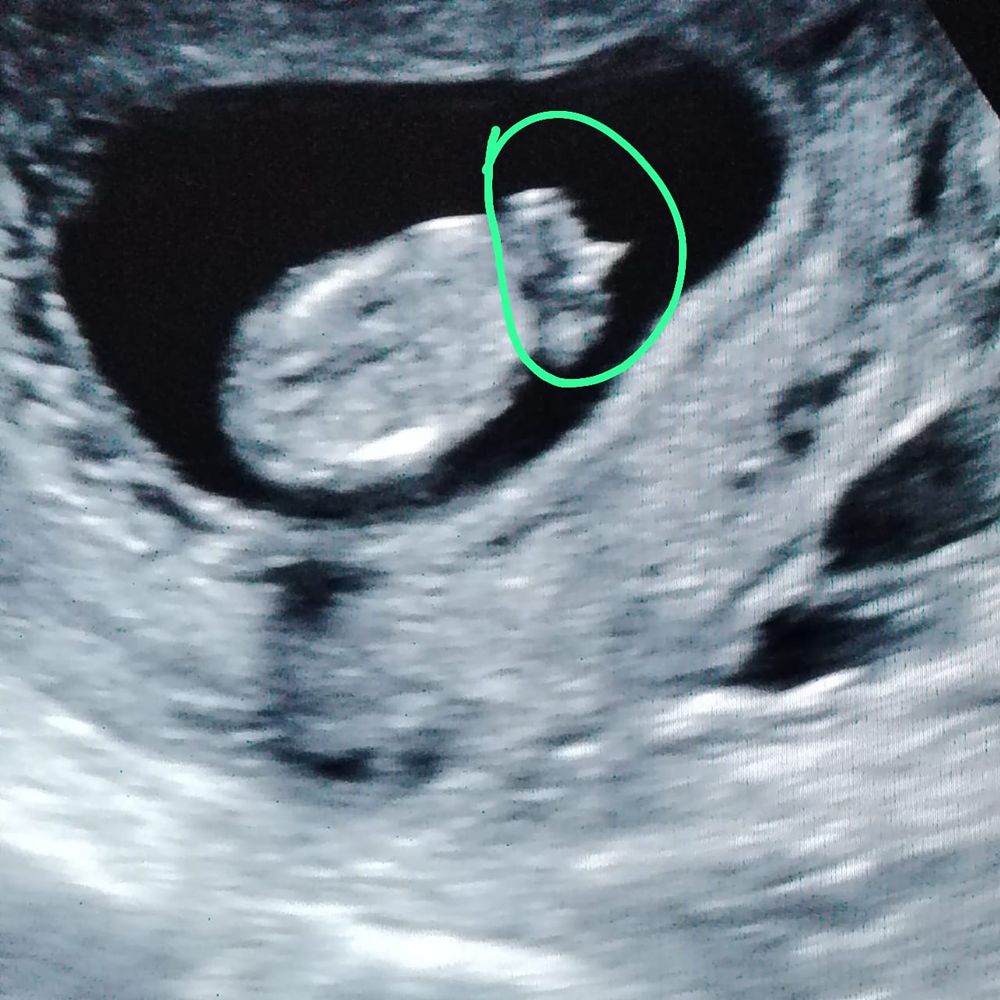

Счастье, не факт у меня был половой бугорок а 13 недель как у мальчика) кровь сдайте 100% покажет

04.02.2025

Ирина Качанова, а было у кого, что бугорок вниз, в потом мальчик?